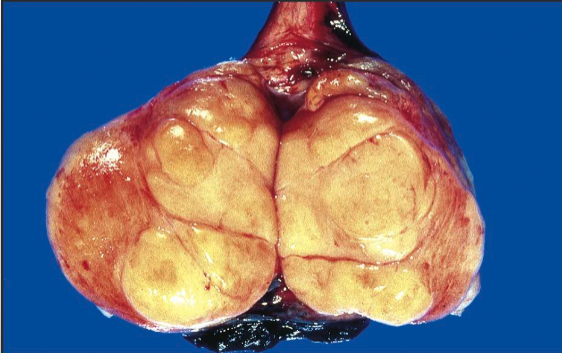

what sub-category of germ cell tumor is described below:

• Malignant

• Never occurs in infants

• Peak incidence-4th decade

• Produces bulky mass

• Gross appearance → Homogenous, gray-white cut surface

seminoma